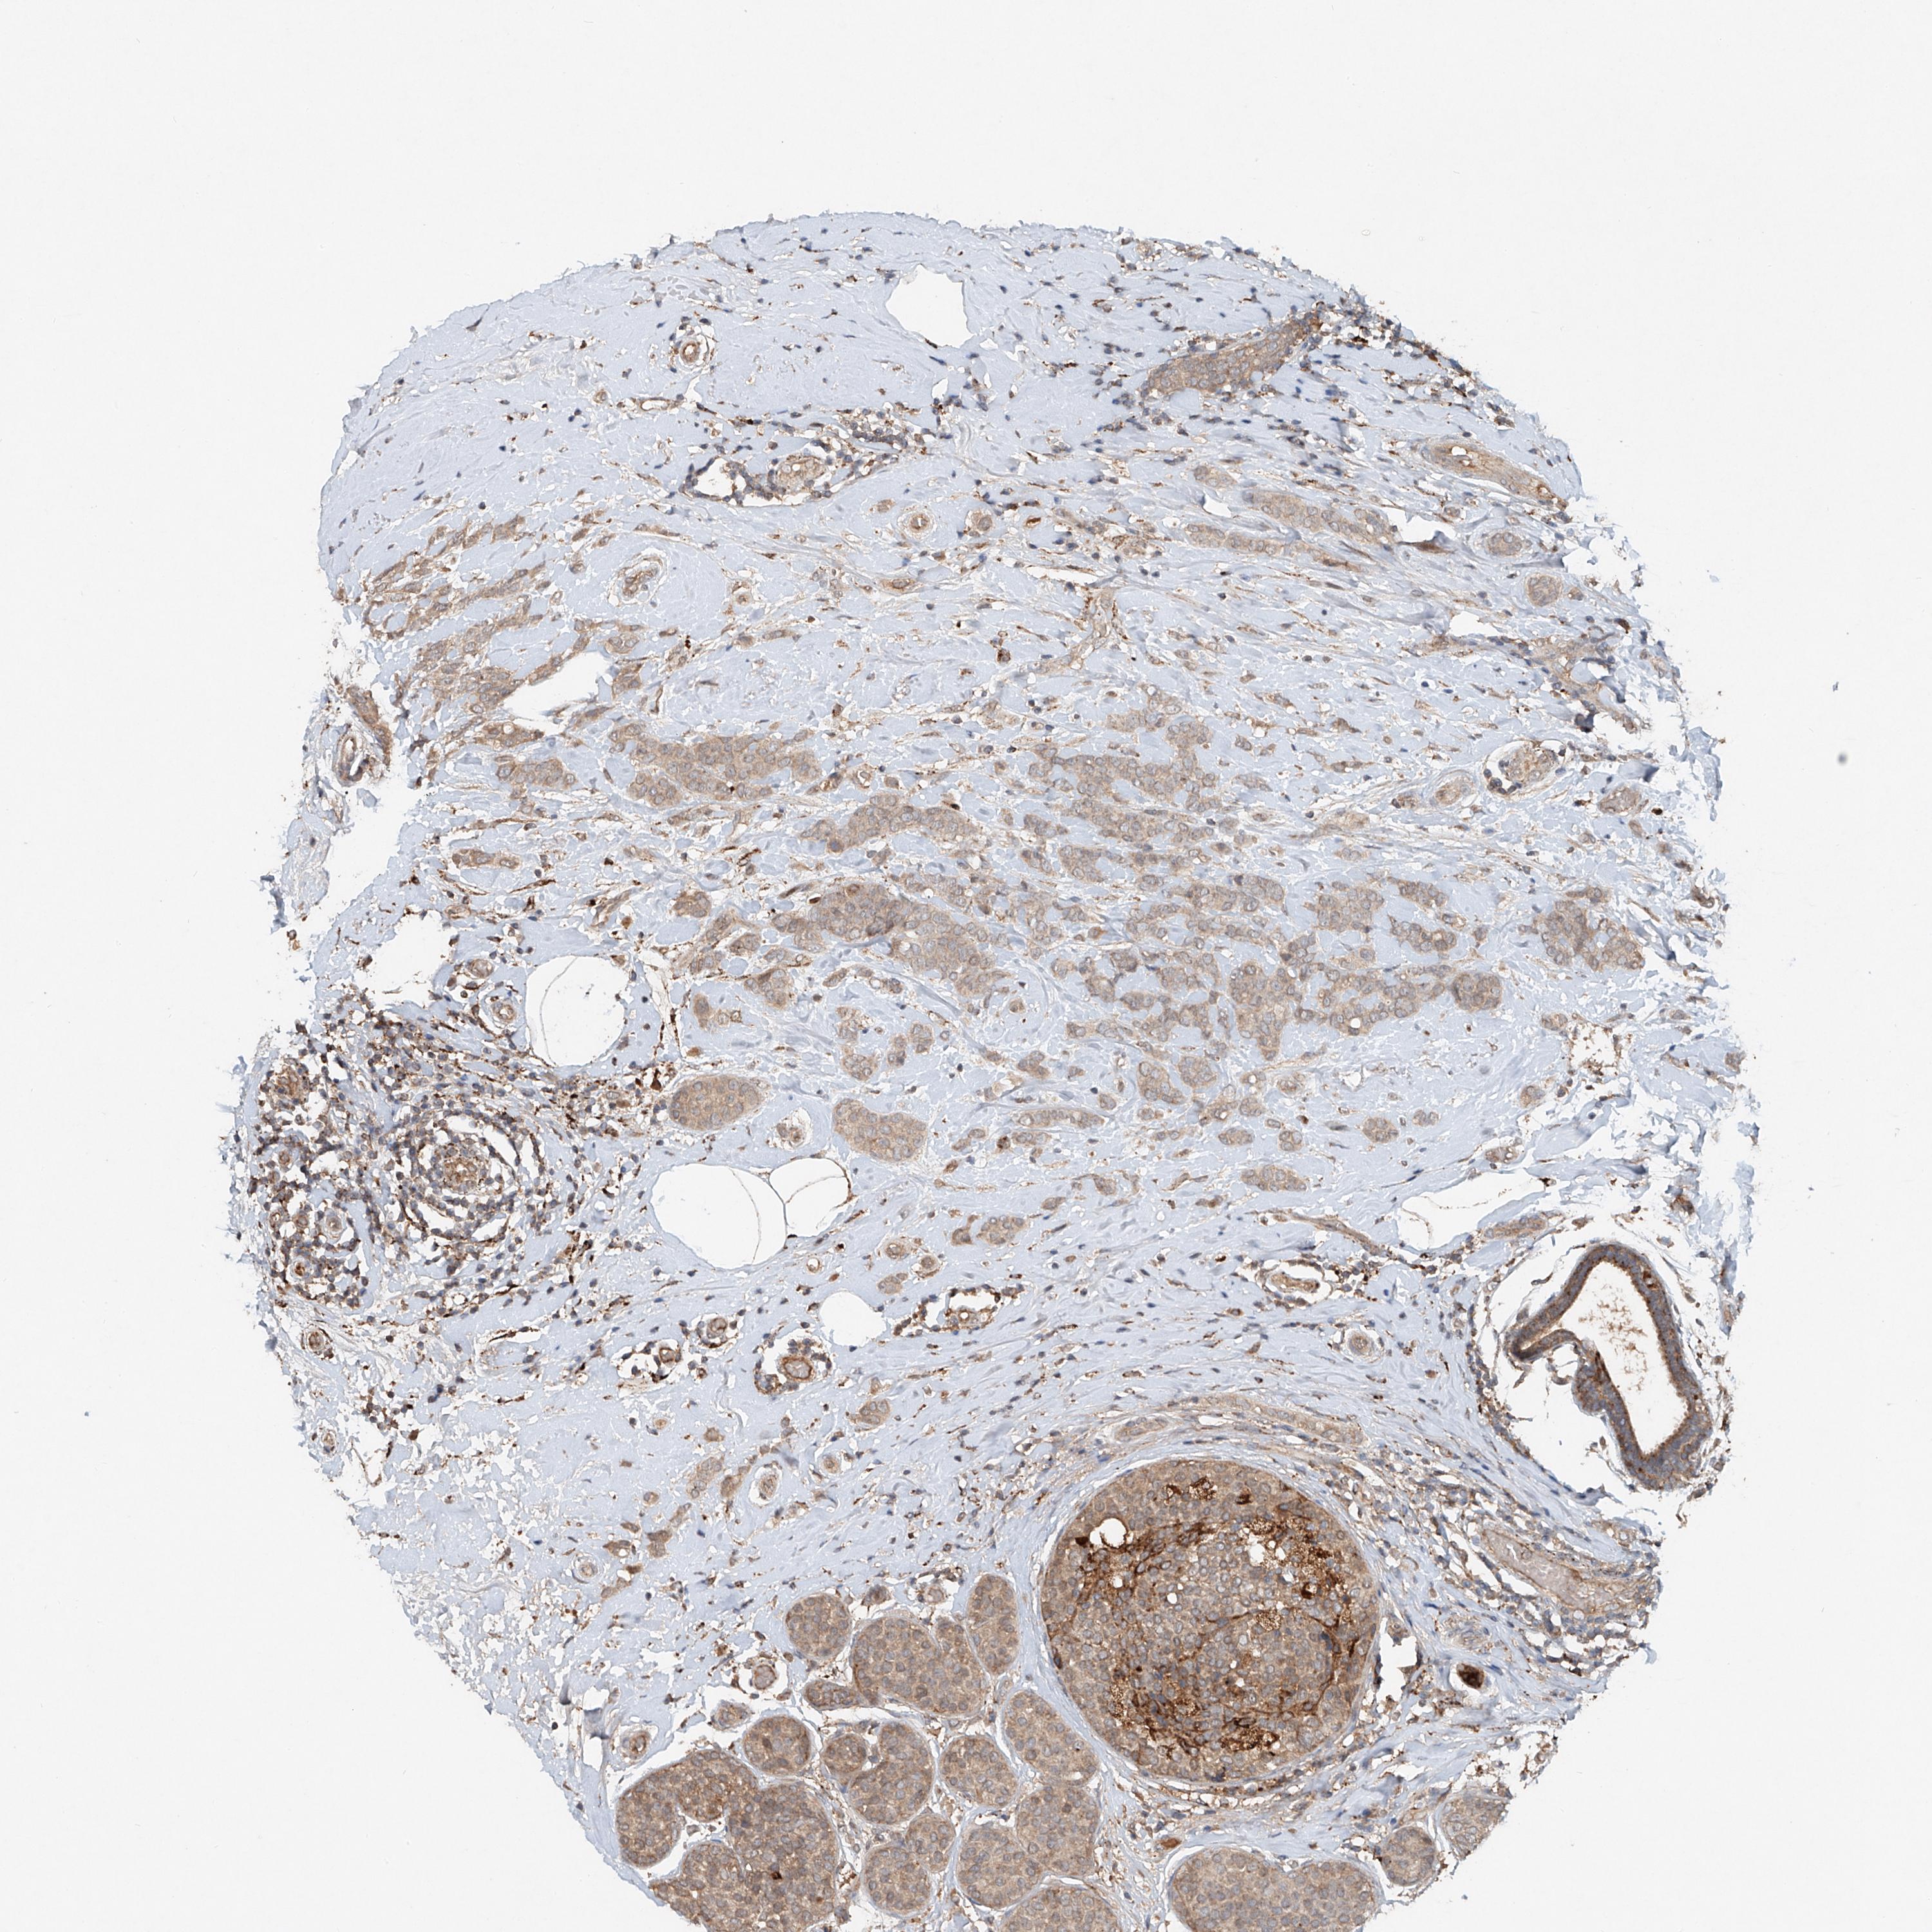

CANCER BREAST CANCER Show tissue menu

BRCA TCGA BRCA VALIDATION PROTEIN EXPRESSION

Breast cancer

Human cancer

Breast invasive carcinoma